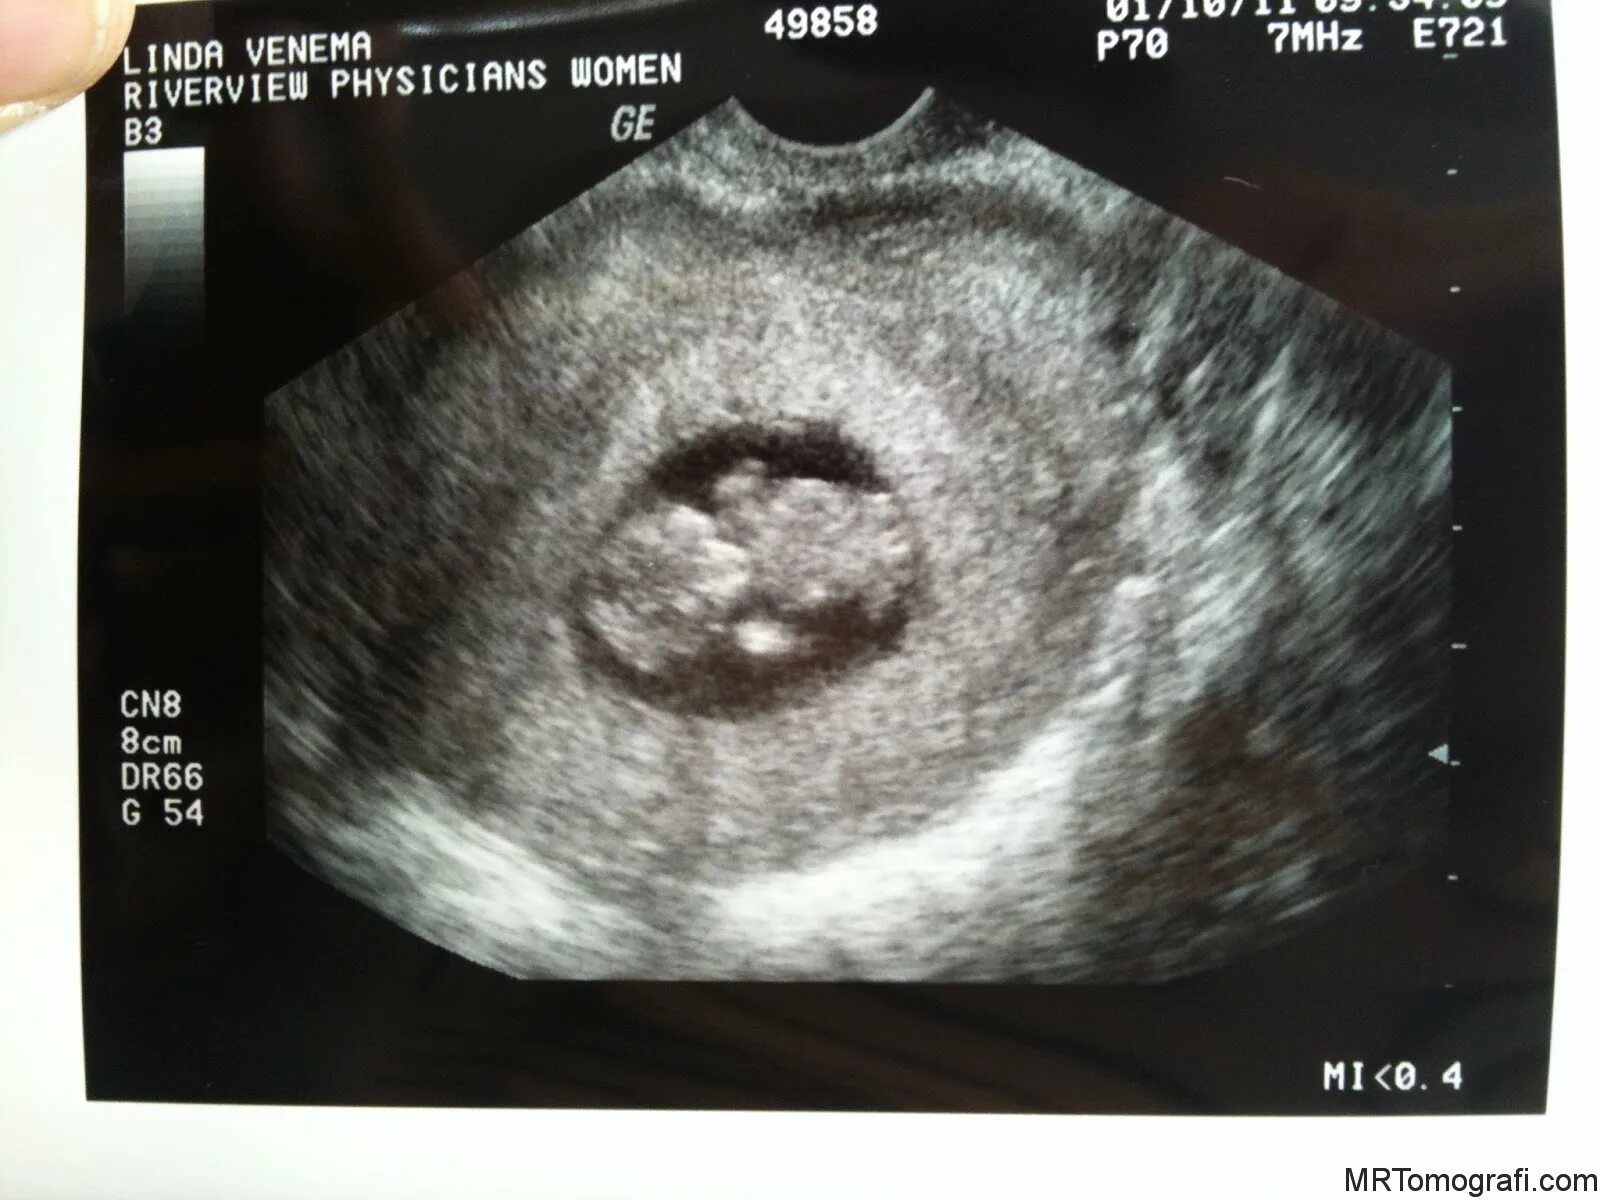

1 9 неделя беременности